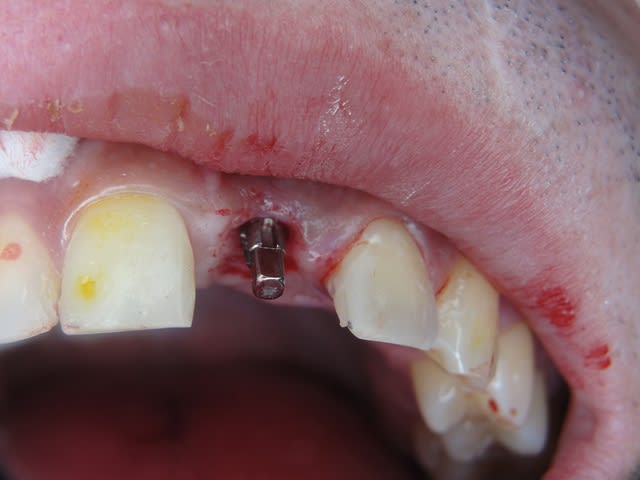

J'ai de tout en boutique..jeune homme 25 ans accident de piscine choc sur la bordure ( fêlure existante..fistule), extraction le jour même, temporisation 4 mois (avec un bout de trombone) Monobloc 16mm 60N, prep cap zircone droit 2/2 provisoire ion, temporisation 3 mois ceramo ceram..

J'ai de tout en boutique..jeune homme 25 ans accident de piscine choc sur la bordure ( fêlure existante..fistule), extraction le jour même, temporisation 4 mois (avec un bout de trombone) Monobloc 16mm 60N, prep cap zircone droit 2/2 provisoire ion, temporisation 3 mois ceramo ceram.. suite des photos :)

Au contraire..si tu regarde attentivement les radios tu veras qu'en quelques mois il y a une néoformation osseuse autour des micros spires. On voit un manque le jour de la pose et plus d'os avec la Procera. Volontairement j'ai pas plus enfoncé l'implant ..Si j'avais ouvert j'aurai bousillé tout le potentiel cicatriciel..Charon l'a démontré depuis longtemps en paro. Aux patient je leur explique que "Ouvrir c'est comme tondre le gazon avec un motoculteur" .

Donc il y maintien et renfort du parodonte.